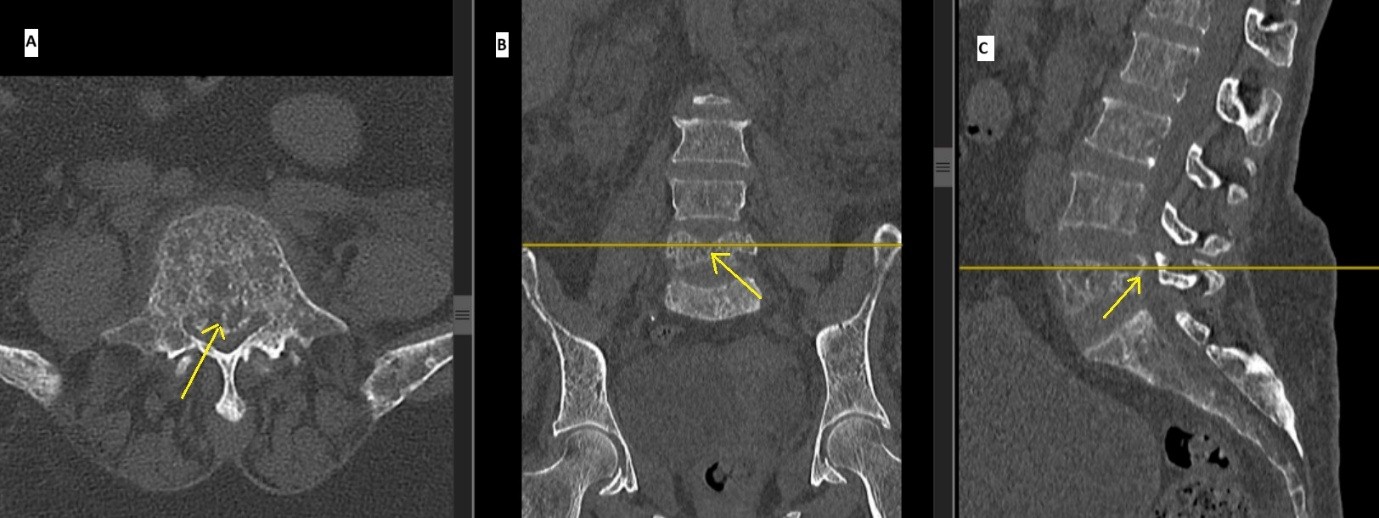

Computed tomography revealed collapse of the L5 vertebral body with retropulsion of bony fragments into the spinal canal (Fig. 2).

Figure 2: Non contrast computed tomography scan images showing collapse of the L5 vertebra causing severe narrowing of spinal canal (a) Axial, (b) Coronal, (c) sagittal cuts.